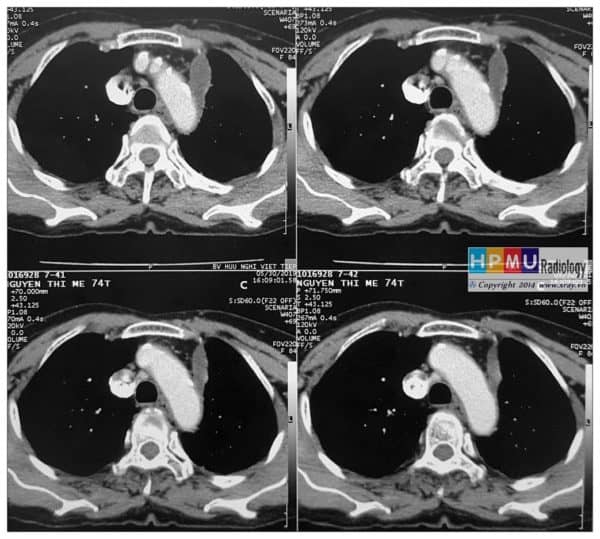

Hạch trung thất

Hạch trung thất - Ảnh 3

» Thông tin: Nữ giới – 74 tuổi.

» Lâm sàng: Đau ngực.